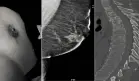

Los marcadores autoinmunes (ANA, ASMA, LKM-1) fueron negativos, al igual que los marcadores tumorales CEA y CA-19-9. La ecografía abdominal mostró hígado graso moderado con dimensiones en límite superior, litiasis vesicular de 0,8 cm y ligera dilatación del colédoco.

Se inició antibioticoterapia intravenosa y rehidratación, sin mejoría inicial. Se realizó CPRE que descartó obstrucción biliar, seguida de resonancia magnética que mostró engrosamiento de pared vesicular. Ante la falta de respuesta, se procedió a biopsia hepática percutánea ecoguiada, la cual reveló colestasis parenquimatosa y canalicular significativa. Se estableció el diagnóstico presuntivo de daño hepático inducido por vinagre de sidra de manzana.